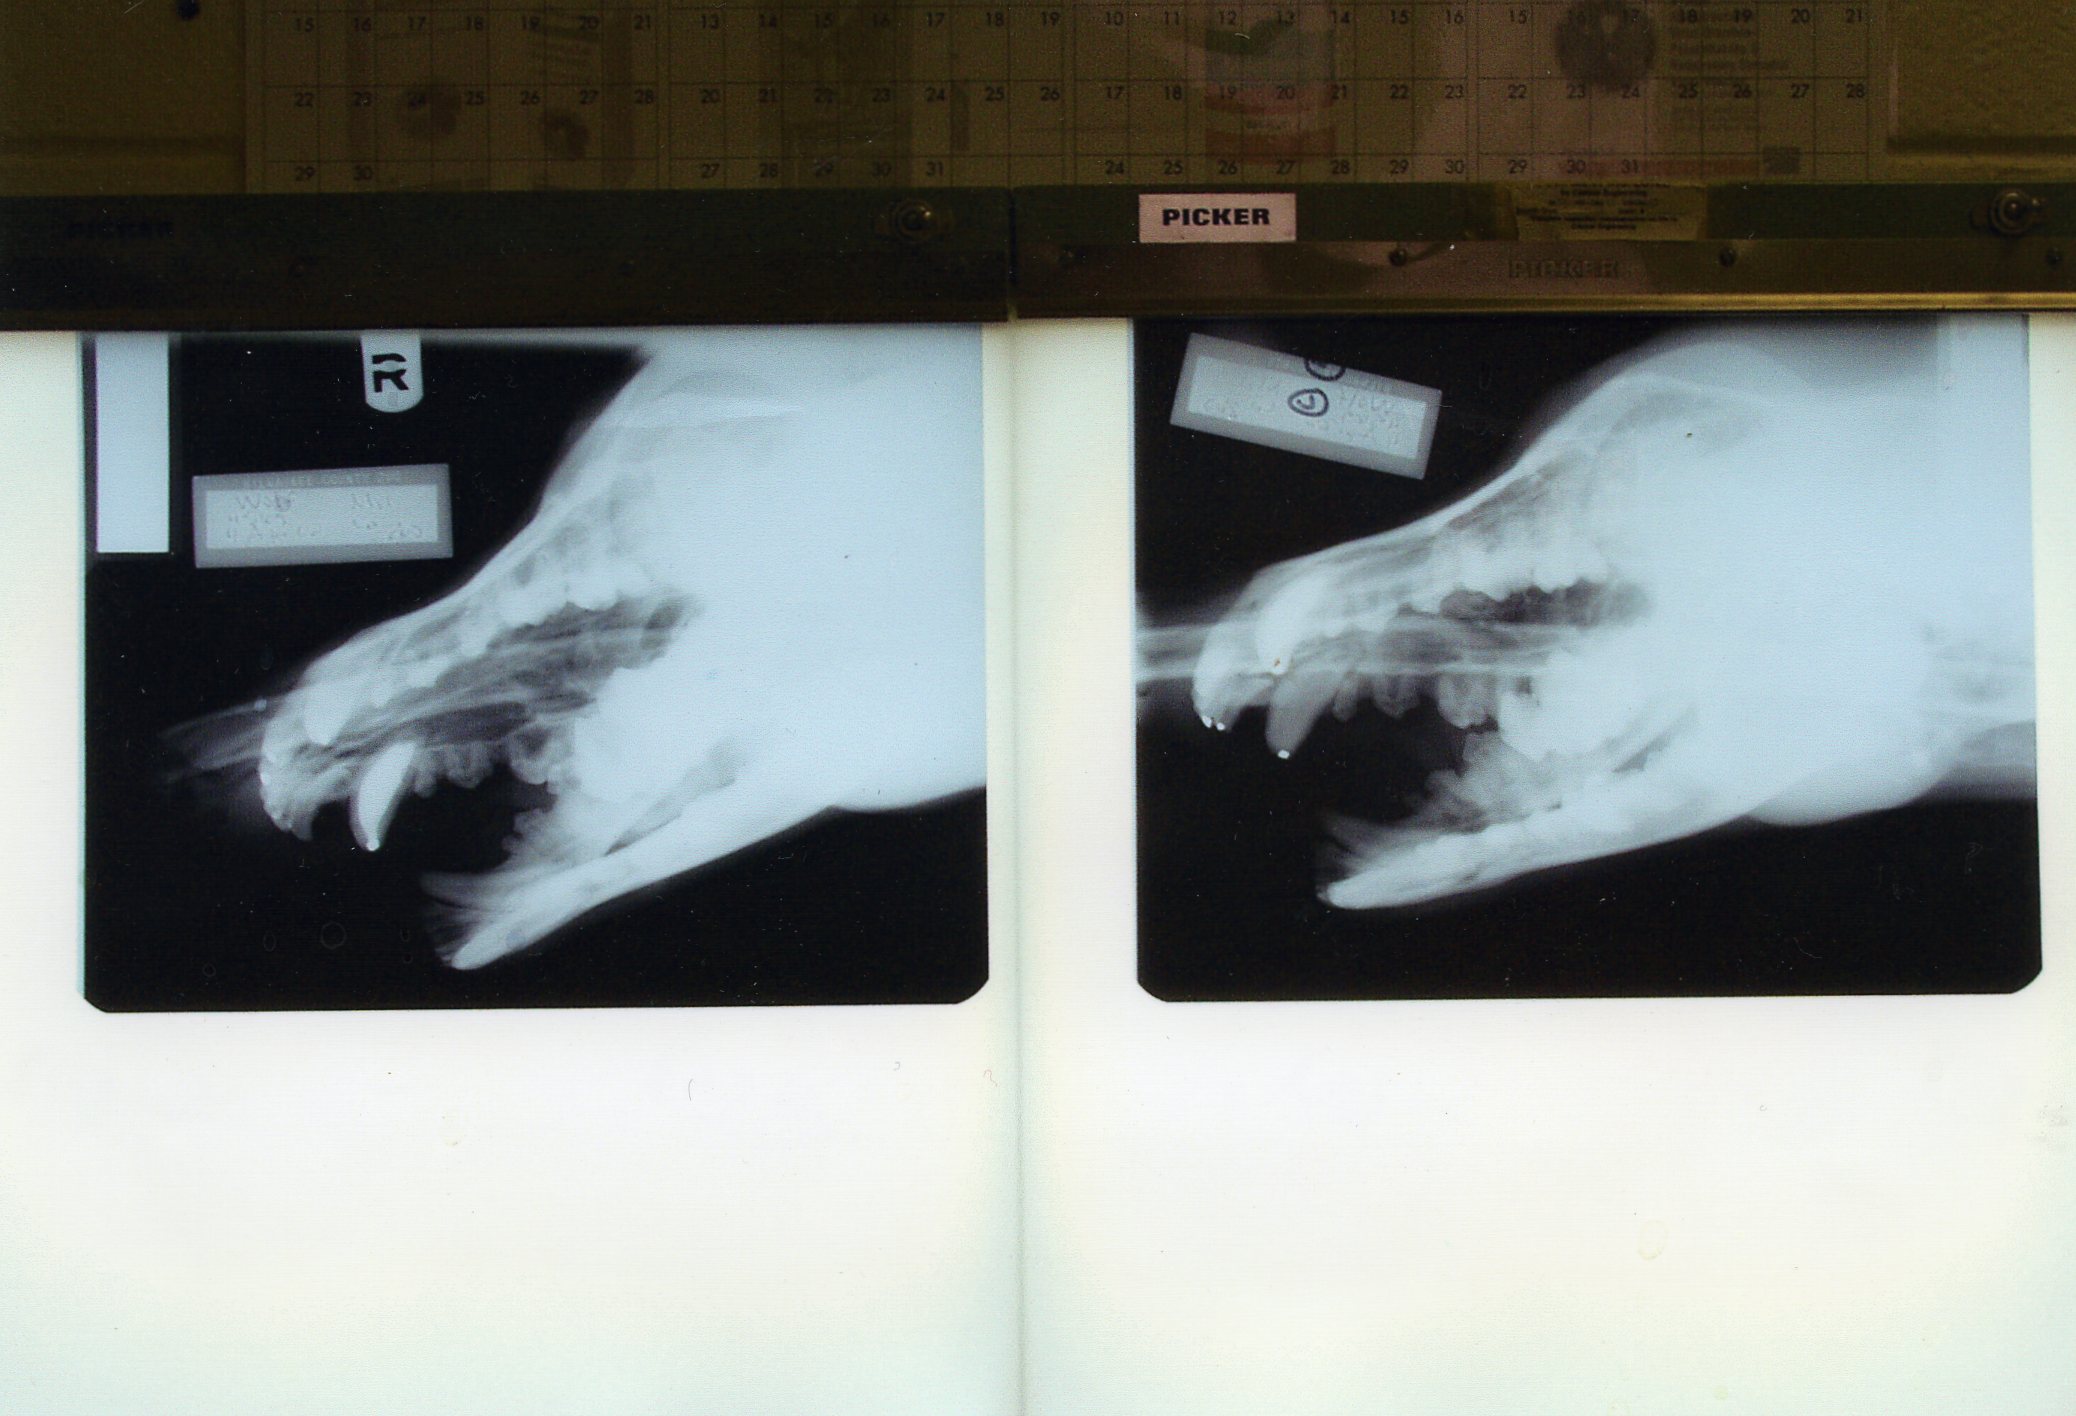

We learned to use the zoo hospital table radiography unit with fine grain and mammography film for full head views that are fully adequate for dental treatment. Right and left obliques are taken at 45 degrees with the mouth open. With proper positioning, each film will isolate one mandibular arch and one maxillary arch. Then with maxillary and mandibular dorsal-ventral intra orals, one will be provided with complete views of the entire arch.